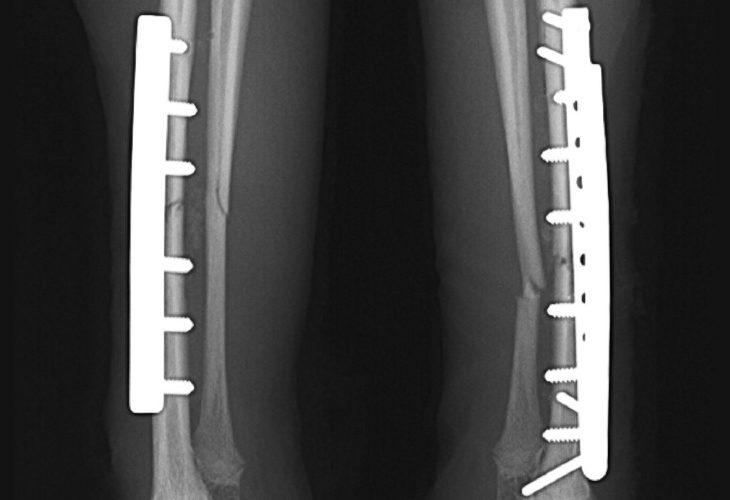

脛骨骨幹部らせん骨折

極小若齢犬橈尺骨骨折